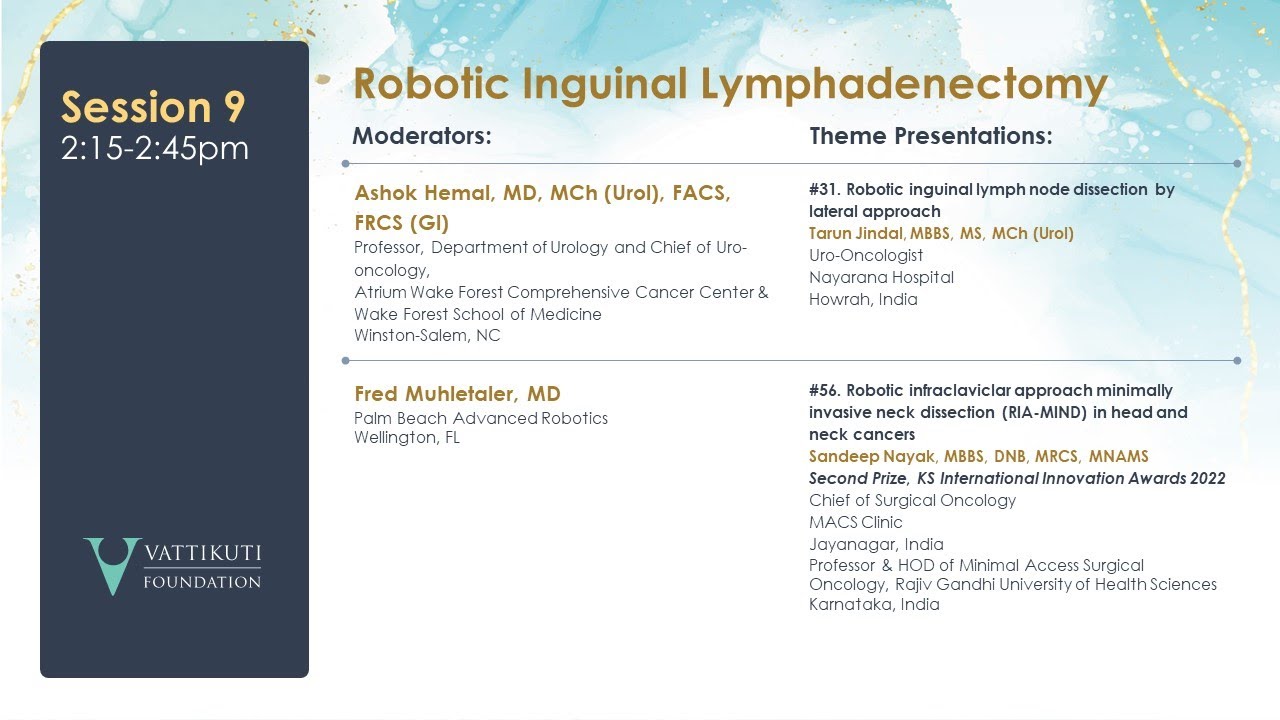

Robotic inguinal lymph node dissection by lateral approach